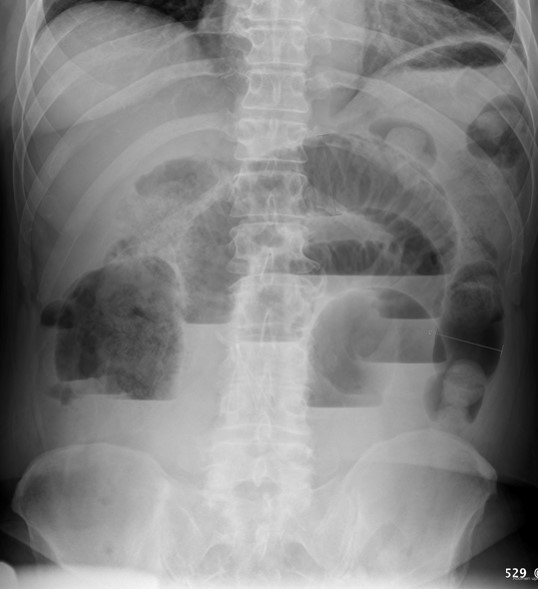

64세 여자가 1일 전부터 토하고 배가 아파서 병원에 왔다. 통증은 주기적으로 쥐어짜는 듯하다고 한다. 10년 전에 위암으로 수술을 받았다. 혈압 123/81 mmHg, 맥박 82회/분, 호흡 20회/분, 체온 37.3 ℃이다. 배는 불러 있고 장음은 증가되어 있으며 배꼽 주위에 경미한 압통이 있다. 혈액검사 결과는 다음과 같다. 복부 X선사진이다. 처치는?

AXR: Step-ladder sign

복부 수술력, 복통/복부팽만/구토, AXR상 step-ladder sign으로 보아 소장 폐쇄 진단 하, 교액의 징후가 명확하지 않으므로 코위관 삽입을 통한 감압 및 보존적 치료를 시행한다.

• AXR상 step-ladder sign이 확인되므로 소장 폐쇄로 진단할 수 있다. 경미한 periumbilical dT와 mild leukocytosis 및 CRP elevation이 존재하나, rT가 존재한다고 주어지지 않았으며 발열이 없고 기타 V/S이 안정적이므로 교액(strangulation)이 발생했다고 보기 어렵다.